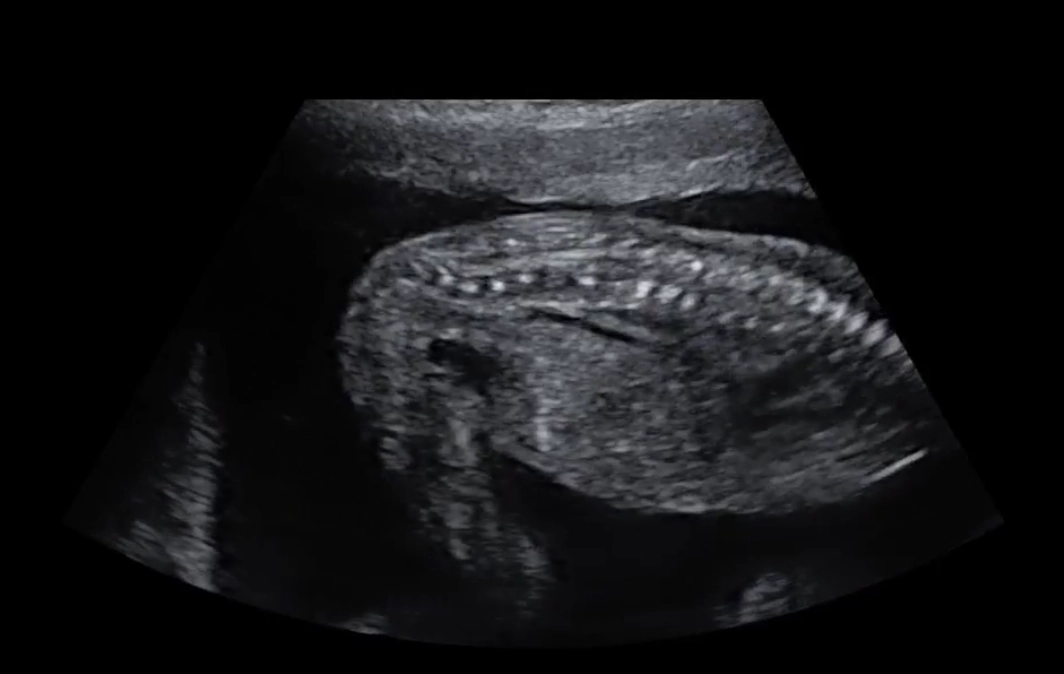

• Loạn sản xương không gây chết

Loạn sản sụn ở trẻ em (Achondroplasia)

• Loạn sản sụn ở trẻ em (Achondroplasia)